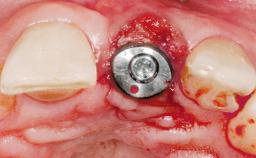

Late Placement of an Implant in a Maxillary Left Central Incisor Site

A 30-year-old female patient had lost tooth 21 and was referred to our clinic for consultation and treatment. Due to advanced apical infection, tooth 21 had been extracted two months earlier at another clinic and an acrylic-resin tooth had been bonded to the adjacent teeth. The patient desired implant treatment to avoid any damage to the adjacent natural teeth. While the patient had no history of any systemic disorder, she was a heavy smoker and exhibited medium to advanced periodontitis in the entire jaw. After the initial treatment to achieve a pocket probing depth of less than 4 mm and no bleeding on probing, a decrease in the height of the papillae mesial and distal to the extraction site and overall gingival recession were observed.

Type of Implants One-Piece|Reduced-Diameter

Bone Augmentation Horizontal|Staged

Augmentation Materials Autogenous chips|Membrane